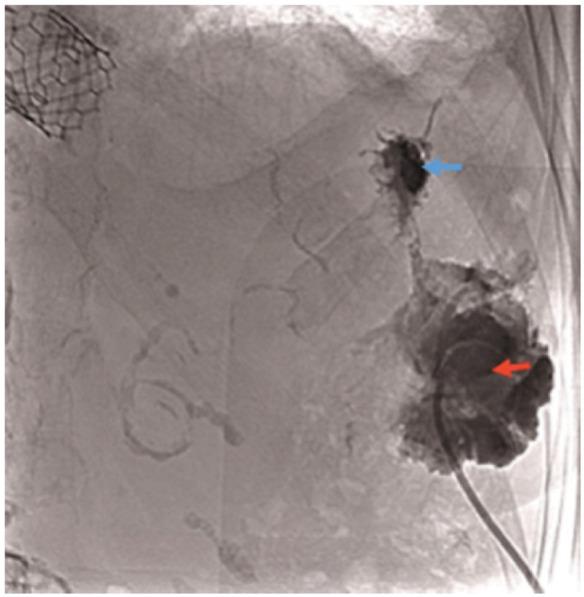

We report an 87-year-old woman treated successfully with 23 mm Sapien 3 transapical transcatheter aortic valve implantation for severe AS. She presented 4 months later with a pulsatile mass in the left breast. After exclusion of other diagnoses, the mass was attributed to a sterile abscess communicating with the pericardial cavity due to post-operative chest infection and pleural effusion. Multimodality imaging helped to define the anatomy of the abscess and the mechanism of the pulsation.

This is the first report of a pulsatile sterile abscess occurring as a complication of transapical aortic valve implantation. Multimodality imaging confirmed that the pulsation was due to extension of the abscess into the pericardial cavity, excluded direct communication with the left ventricle, and facilitated successful non-surgical management.

我们报告了一名87岁女性,因严重AS成功接受了23mm Sapien 3经心尖经导管主动脉瓣植入术。4个月后,她左侧乳房出现搏动性肿块。排除其他诊断后,该肿块归因于术后胸部感染和胸腔积液导致的与心包腔相通的无菌性脓肿。多模态成像有助于明确脓肿的解剖结构和搏动机制。

这是首例经心尖主动脉瓣植入术后出现搏动性无菌性脓肿并发症的报告。多模态成像证实搏动是由于脓肿延伸至心包腔,排除了与左心室的直接相通,并有助于成功进行非手术治疗。